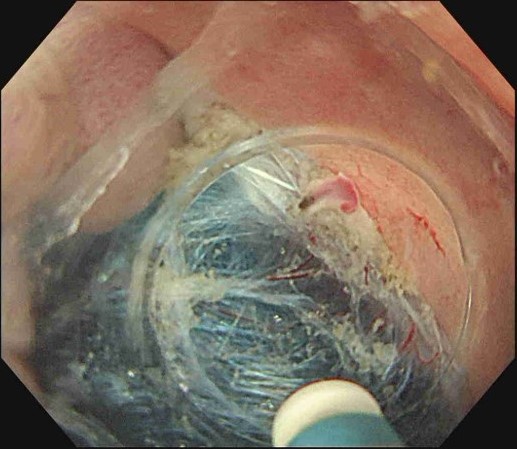

ESD(内視鏡的粘膜下層剥離術)

- 内視鏡先端から出した電気メスで、周囲を切開し、粘膜の下の組織(粘膜下層)をはがしながら切除

- より精密で高度な方法

ESDの手順

Figures adapted from: Nagata M. Endoscopy 2024; 56: E699–E700.

Licensed under CC BY 4.0 (https://creativecommons.org/licenses/by/4.0/)